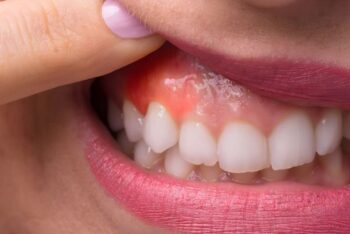

6歯茎が腫れる主な原因と治療法:Vol.3 歯周病

歯茎の腫れの原因が歯周病である場合、歯周病が重症なケースが多いです。

重症化した歯周病では歯を支える歯槽骨が大きく溶け、それに伴い歯周ポケットが深くなります。歯周ポケットが深くなると、歯の周りに細菌がたくさん溜まってしまうので、歯茎が化膿して腫れやすくなります。

歯周病治療は、まず歯の周りに付着している歯垢や歯石を徹底的に除去することにより改善を図ります。

しかし、化膿するほど歯ぐきが腫れている場合は、歯周ポケットが深すぎるため、歯の根の表面に強固に付着している歯石を肉眼や拡大鏡で目視して除去するのはとても難しく、歯石を取り残してしまい、歯周病を改善できずに抜歯されてしまうこともあります。